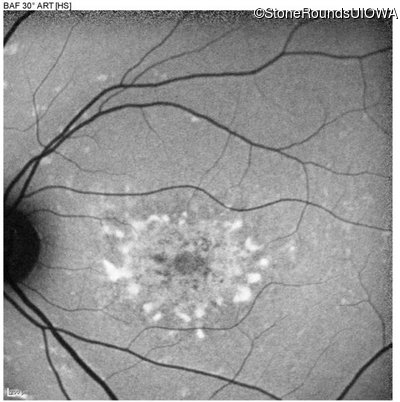

Age at visit: 22 years

Age at visit: 17 years

Age at visit: 18 years

Age at visit: 19 years